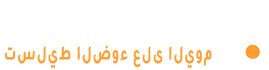

وفيما يتعلق بالكشف المبكر، يوضح الدكتور جعفر أن التصوير المقطعي منخفض الجرعة (LDCT) يعد اليوم الأداة الأكثر فعالية، حيث أظهرت دراسات عالمية انخفاضا في الوفيات بنسبة تتراوح بين 20% و24% لدى الفئات عالية الخطورة، وخاصة المدخنين الحاليين أو السابقين ممن تجاوزت مدة تدخينهم 20 سنة.

ويشرح أن التقدم العلمي كشف أن سرطان الرئة ليس مرضا واحدا، بل مجموعة أمراض تختلف باختلاف الطفرات الجينية. وتعمل المختبرات الحديثة على تحليل طفرات مثل EGFR، ALK، ROS1، KRAS، MET وغيرها، ما يسمح باختيار العلاج الموجه الأكثر ملاءمة لكل حالة.

ويختتم الدكتور حسان جعفر بالتأكيد على أن سرطان الرئة لم يعد حكما نهائيا كما كان ينظر إليه سابقا، لافتا إلى أن الاكتشاف المبكر واستخدام العلاجات الحديثة يمنحان المريض فرصة حقيقية للحياة. ويوصي المدخنين بإجراء الفحص السنوي دون انتظار ظهور الأعراض، مؤكدا أن الوقاية تبدأ بالإقلاع عن التدخين وتحسين جودة الهواء واعتماد نمط حياة صحي، بينما يحمل المستقبل آفاقا واعدة مع دخول تقنيات الذكاء الاصطناعي لتحديد الأنماط الدقيقة في صور الأشعة وتوقع تطور المرض بدقة أعلى.